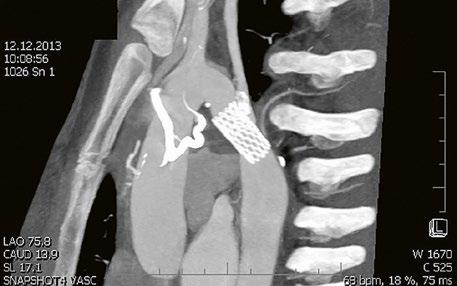

Morfologicky vhodné defekty typu secundum lze uzavřít katetrizační cestou, pomocí okluderu (Obr. 45.13, Video 45.9), defekty nevhodné nebo rizikové ke katetrizačnímu uzávěru jsou uzavírány chirurgicky, často z minitorakotomie nebo torakoskopicky roboticky. Defekty typu sinus venosus, koronárního sinu nebo primum lze řešit pouze chirurgickým uzávěrem. Při současné významné trikuspidální nebo mitrální regurgitaci je vhodné doplnit plastiku chlopně, při flutteru nebo fibrilaci síní pravostranný nebo oboustranný MAZE.

Obr. 45.13 Amplatzerův okluder uzavírající defekt septa síní II (3DE TEE)

Video 45.9 3DE TEE

Amplatzerův okluder uzavírající defekt septa síní II